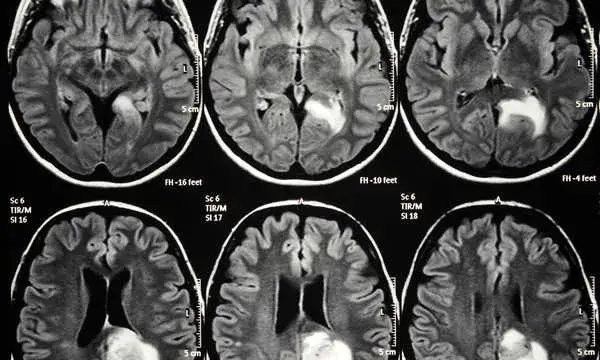

Stwardnienie rozsiane (SM) a zaburzenia nastroju: Co wykaże MRI?

Stwardnienie rozsiane (SM) to przewlekła choroba autoimmunologiczna, która atakuje osłonki mielinowe nerwów w mózgu i rdzeniu kręgowym. Charakterystyczne dla SM zmiany demielinizacyjne są doskonale widoczne w badaniu MRI jako ogniska zapalne lub blizny. Co ciekawe, SM często idzie w parze z objawami psychiatrycznymi. Wielu pacjentów doświadcza depresji, lęku, zaburzeń nastroju, a także problemów poznawczych, takich jak trudności z koncentracją czy przetwarzaniem informacji. MRI jest złotym standardem w diagnozowaniu SM, pozwalając na wizualizację tych zmian i odróżnienie ich od innych schorzeń, a tym samym na wdrożenie odpowiedniego leczenia neurologicznego, które często poprawia również samopoczucie psychiczne.